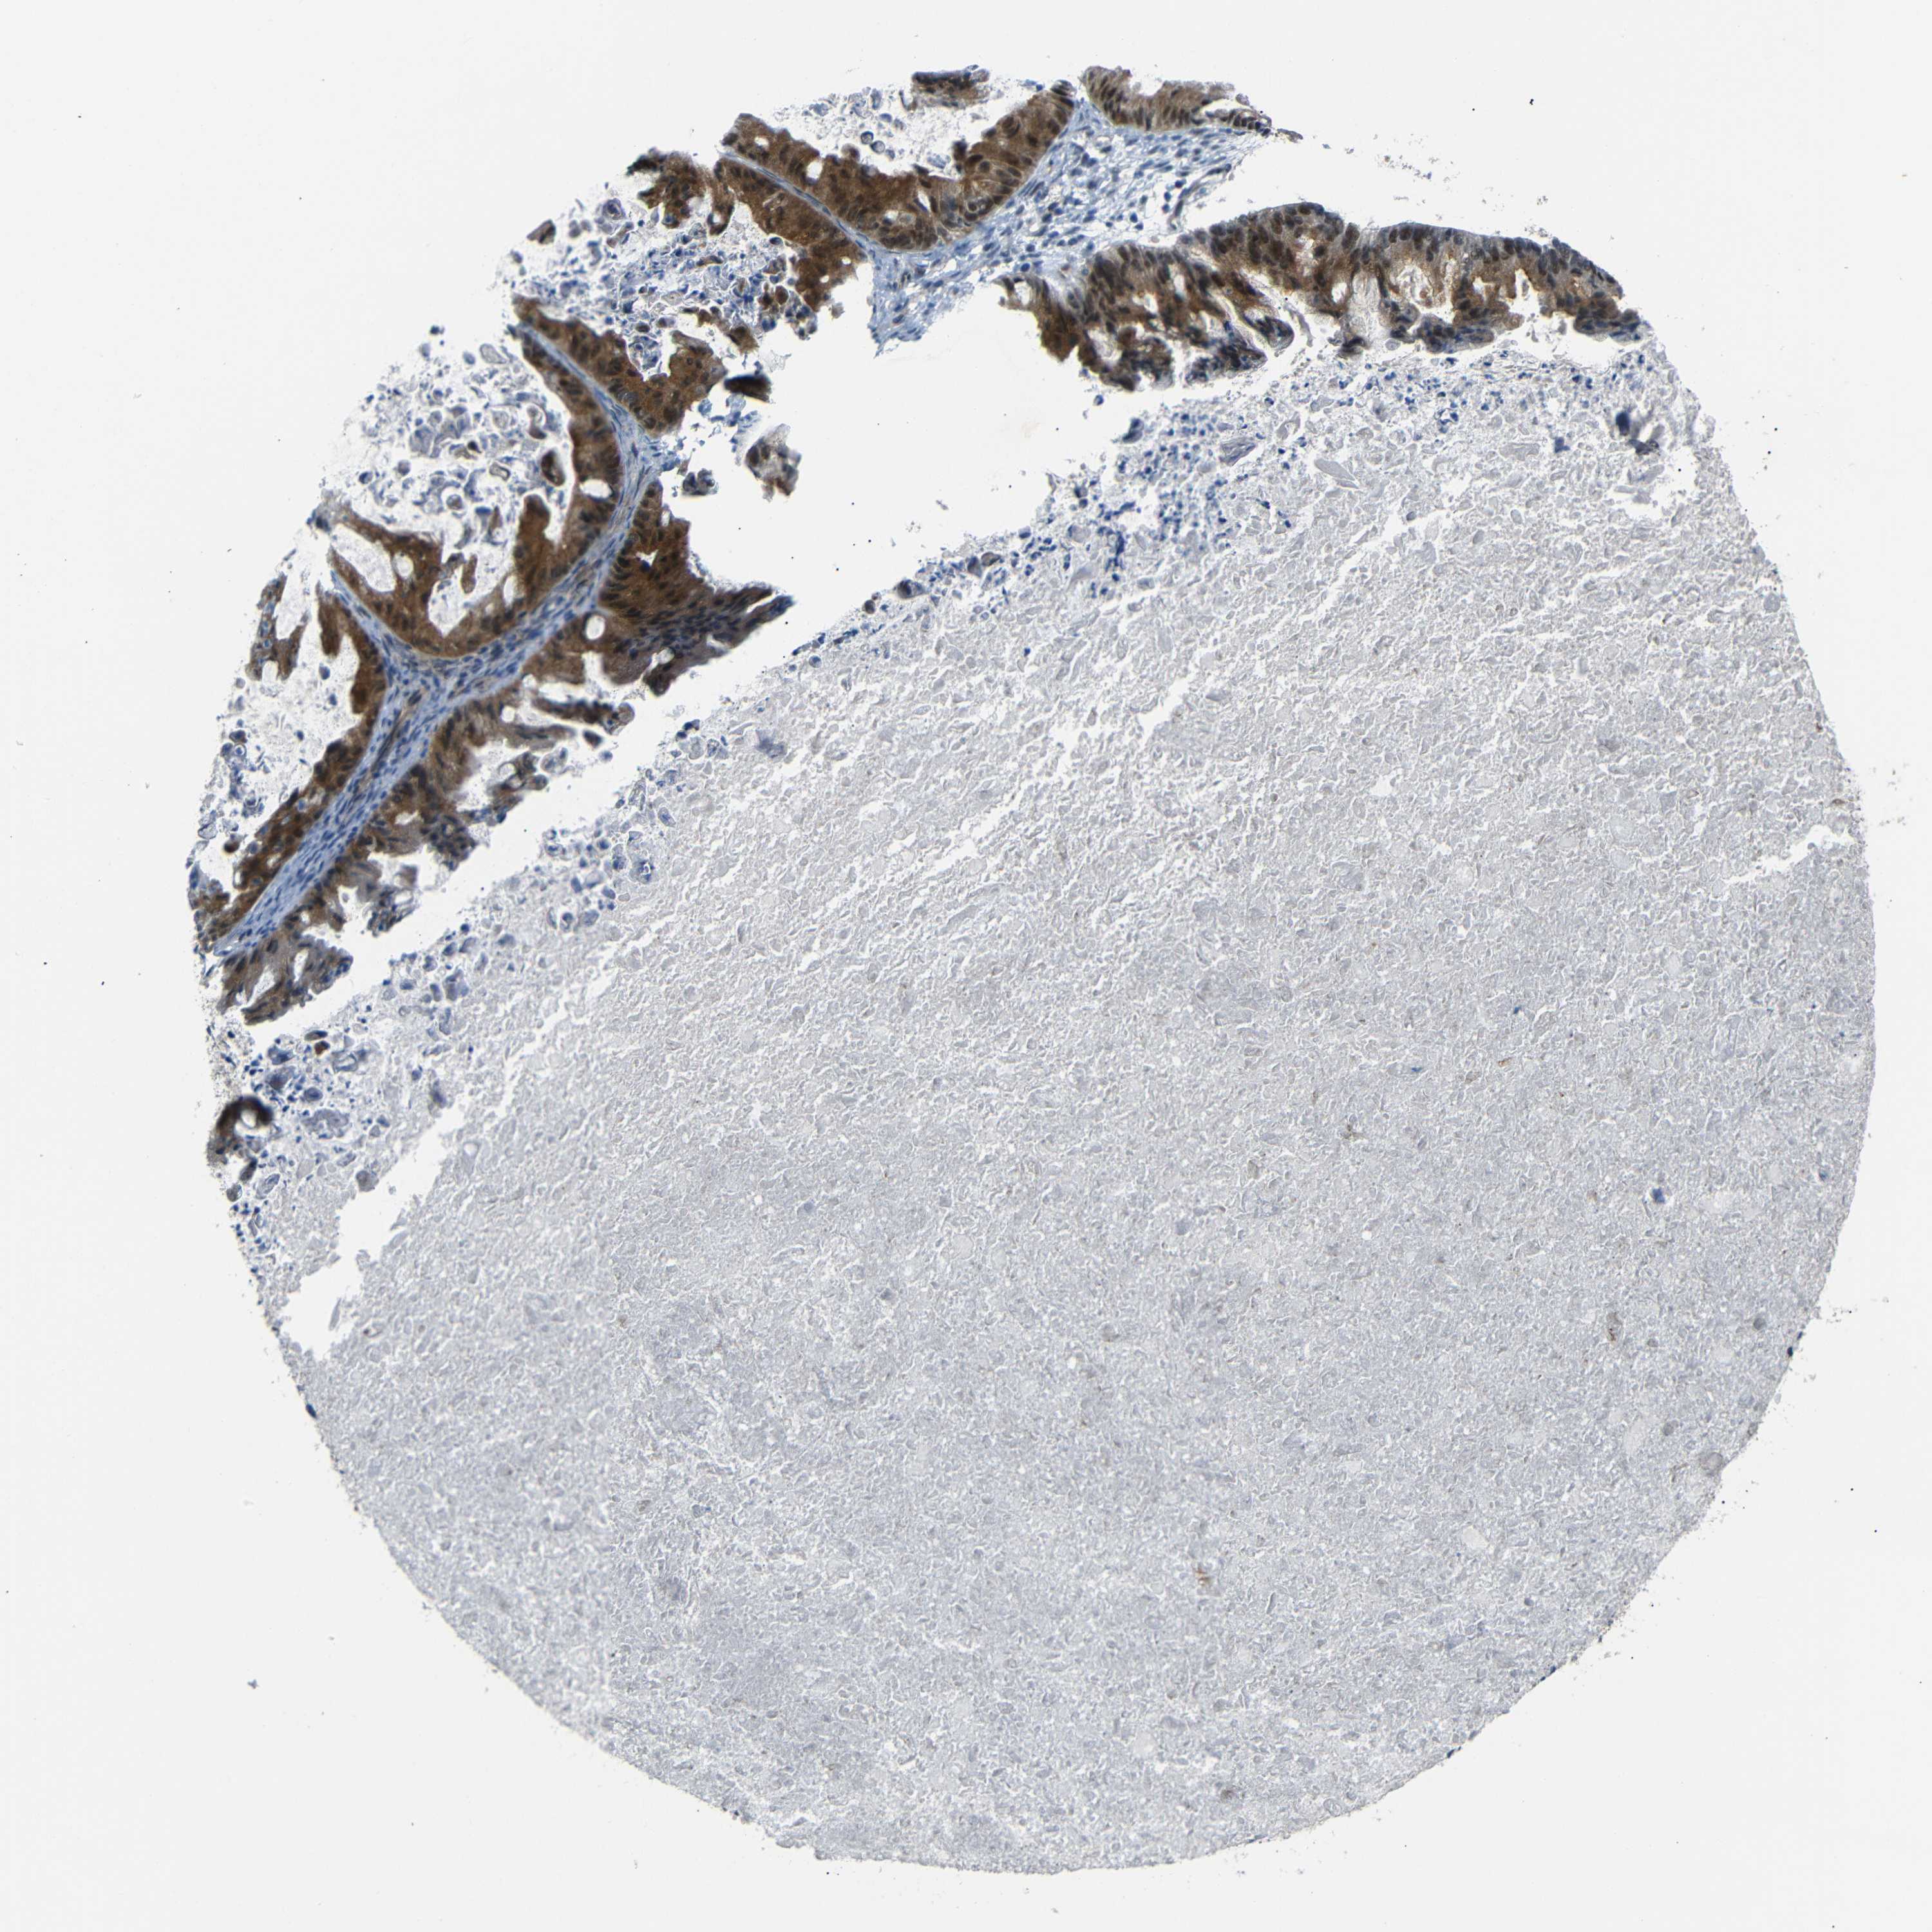

OVARIAN CANCER - Protein expressioni

A mouse-over function shows sample information and annotation data. Click on an image to view it in a full screen mode. Samples can be filtered based on level of antibody staining by selecting one or several of the following categories: high, medium, low and not detected. The assay and annotation is described here.

Note that samples used for immunohistochemistry by the Human Protein Atlas do not correspond to samples in the TCGA dataset.

Antibody stainingi

Antibody staining in the annotated cell types in the current human tissue is reported as not detected, low, medium, or high, based on conventional immunohistochemistry profiling in selected tissues. This score is based on the combination of the staining intensity and fraction of stained cells.

Each image is clickable and will lead to virtual microscopy that enables deeper exploration of all samples and also displays staining intensity scores, fraction scores and subcellular localization as well as patient and tissue information for each sample.

Antibody HPA013328

Staining

High

Medium

Low

Not detected

Intensity

Strong

Moderate

Weak

Negative

Quantity

>75%

75%-25%

<25%

None

Location

Nuclear

Cytoplasmic/membranous

Cytoplasmic/membranous,nuclear

Cystadenocarcinoma, serous, NOS

Carcinoma, endometroid

Cystadenocarcinoma, mucinous, NOS

Carcinoma, NOS